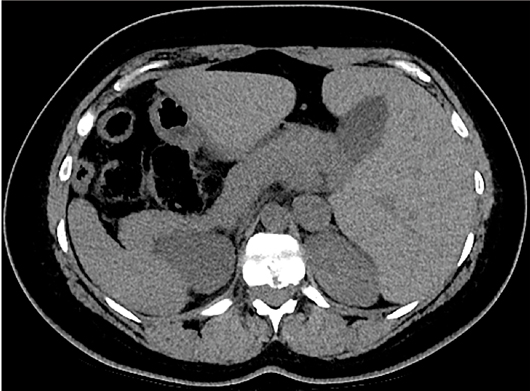

The CT scout image demonstrated dextrocardia, the heart situated on the right side of the body with the cardiac apex pointing to the right (Figure 1). CT of the abdomen and pelvis, in axial and coronal planes, revealed a mirror-image transposition of the abdominal organs. The liver, gallbladder, and biliary system were located on the left side of the body. The spleen was abnormally located in the right upper abdominal quadrant. The stomach and descending colon were noted to be on the right side of the body, while the ascending colon was on the left side of the body. The abdominal aorta was positioned to the right of the inferior vena cava (Figures 2–5).

Figure 4